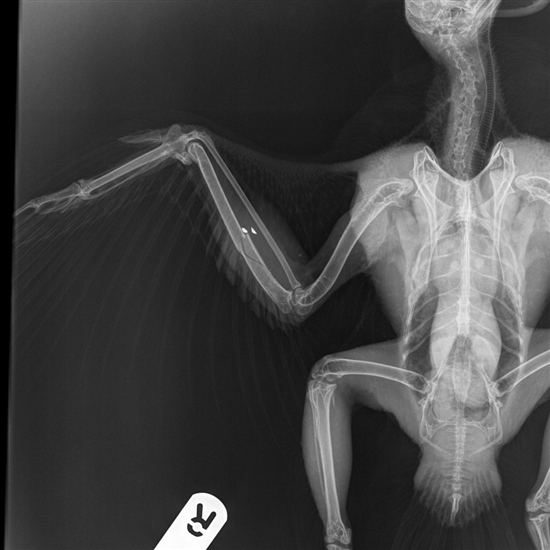

Last year we blogged about a peregrine that had been found shot in Hampshire. His colour ring (Blue GX) identified him as ‘Peter’, one of the chicks that successfully fledged from Salisbury Cathedral in 2014. He’d suffered a fractured wing from the gunshot fragments.